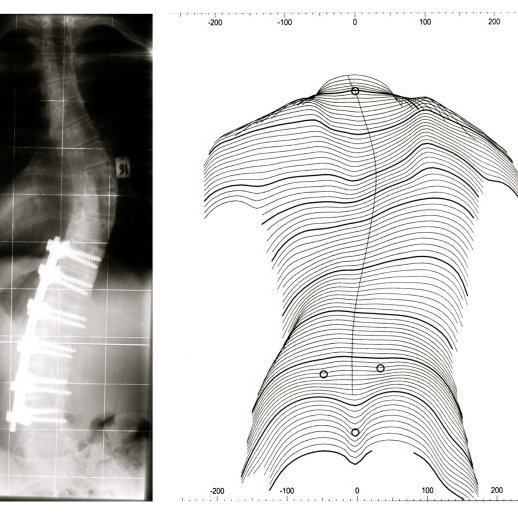

Surgical intervention may be recommended for severe cases of scoliosis or when non-surgical approaches have been ineffective. The most common surgical procedure for scoliosis is spinal fusion, where the vertebrae are fused together to correct the curvature. This procedure aims to stabilize the spine, reduce pain, and prevent further progression of the deformity.